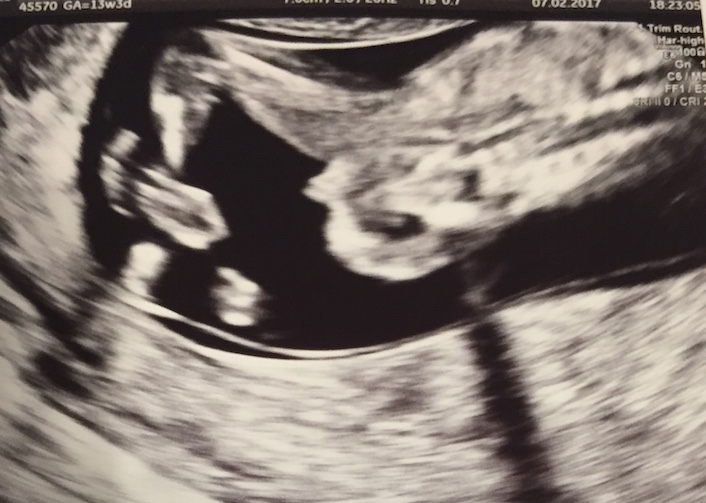

Tricky Nub.. Boy or Girl? 13+3

Four weeks ago I had a scan and the doctor gave me this picture. It was pretty hard to get it, because he/she was moving and jumping a lot.

Attachment 35355